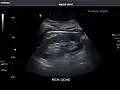

Kidneys: Right and left kidneys measure 11.5 cm and 12 cm in length respectively. No hydronephrosis. Small left lower pole kidney cyst.

Left kidney -